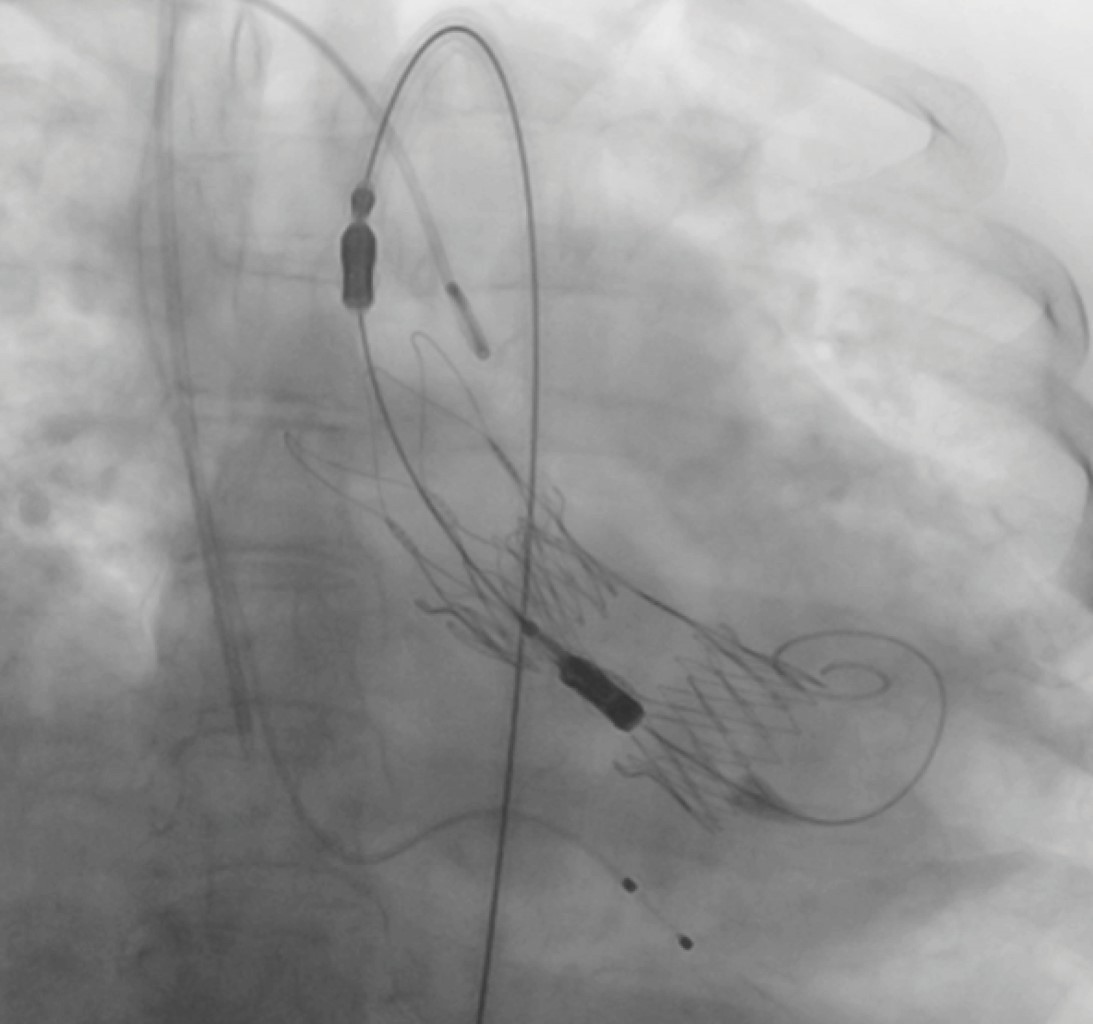

Due to this complication, the patient was taken to the operating room for extraction of the migrated valve and aortic valve replacement. Under cardiopulmonary bypass, the migrated valve was extracted from the left ventricle, along with the second implanted prosthesis (Figures 2 and 3). Subsequently, an aortic ring enlargement using the Nicks technique was performed, and the valve was replaced with a SJM™ Masters Series 21 mm (St Jude Medical, Inc., USA) mechanical prosthesis. Finally, a chest drainage tube was placed in the retrosternal space, and the procedure was completed without complications, with a total cardiopulmonary bypass time of 115 minutes and an aortic clamping time of 94 minutes.

Figure 2

Figure 3